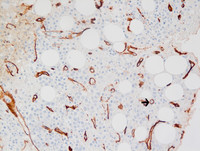

Figure 3: CD34 in Paroxysmal Nocturnal Hemoglobinuria

A bone marrow biopsy with immunohistochemical staining for CD34 highlights scattered CD34 positive blasts (arrow) and blood vessels.